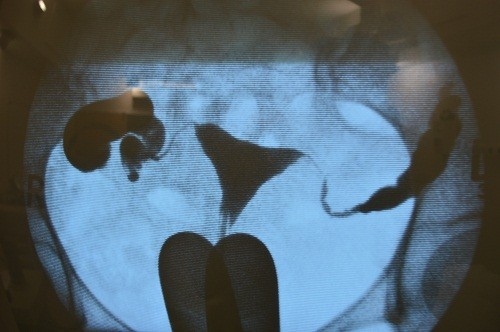

– Trong xét nghiệm này, một loại thuốc nhuộm (tương phản vật chất) được đưa qua một ống nhỏ từ âm đạo vào tử cung. Bởi vì tử cung và ống dẫn trứng nối với nhau, thuốc nhuộm sẽ chảy vào ống dẫn trứng. Nhờ đó hình ảnh chụp X quang có thể hiển thị các vấn đề ở tử cung hoặc ống dẫn trứng, chẳng hạn như tắc nghẽn ống dẫn trứng hoặc hình dạng tử cung bất thường.

– Tiếp đến bơm một ít dung dịch có chứa thuốc nhuộm vào buồng tử cung. Nếu ống dẫn trứng thông suốt, dung dịch cản quang sẽ đi vào hai ống dẫn trứng và ổ bụng. Sau chụp nếu thấy có hình ảnh thuốc cản quang trong bụng thì kết luận 2 buồng trứng thông suốt.